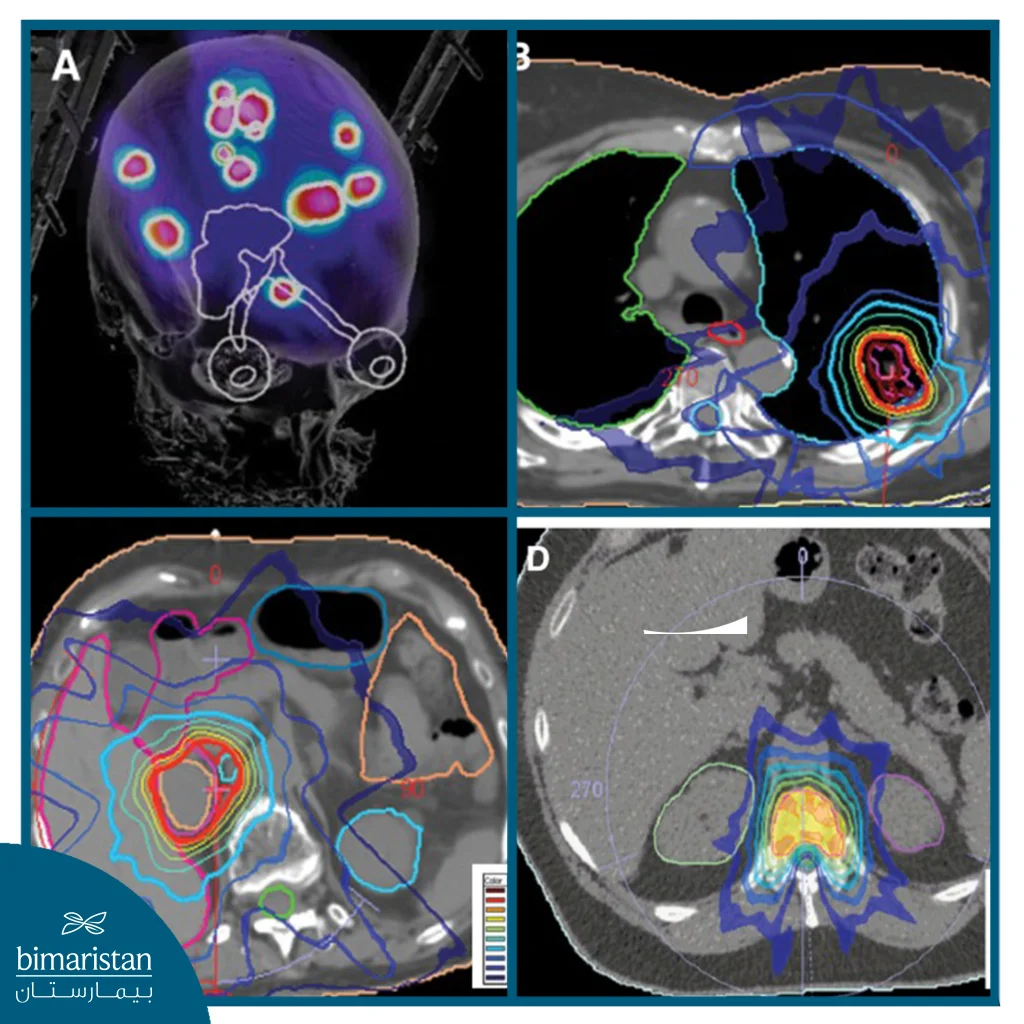

Stereotactic body radiotherapy is a cancer treatment that uses 3D or 4D imaging and precisely focused beams of radiation to deliver high doses to the target area while minimizing damage to surrounding healthy tissue. As with other forms of radiotherapy, stereotactic radiotherapy works by damaging DNA in tumor cells. Radiation-induced damage prevents cells from forming additional tumor cells. This causes tumors to shrink.

Stereotactic radiotherapy targets small tumors with high precision using concentrated doses of radiation. This technique is accurate to within 1 mm, does not require surgery, and can be performed on an outpatient basis. The radiation can be delivered using a frameless system or a conventional framed system. The beams are directed at the tumor to conform to its shape, allowing cancer cells to be destroyed while sparing the surrounding healthy tissue.

- Computerized treatment planning: The treatment team uses the images obtained to design an accurate 3D plan that determines the optimal radiation angles, directions, and dose to target only the tumor while minimizing damage to healthy tissue.

- Carrying out treatment: The Linear Accelerator or CyberKnife system rotates around the patient at multiple angles, directing multiple precise beams of high-energy radiation toward the tumor to intersect at the target point with pinpoint accuracy, destroying cancer cells without damaging surrounding healthy tissue.